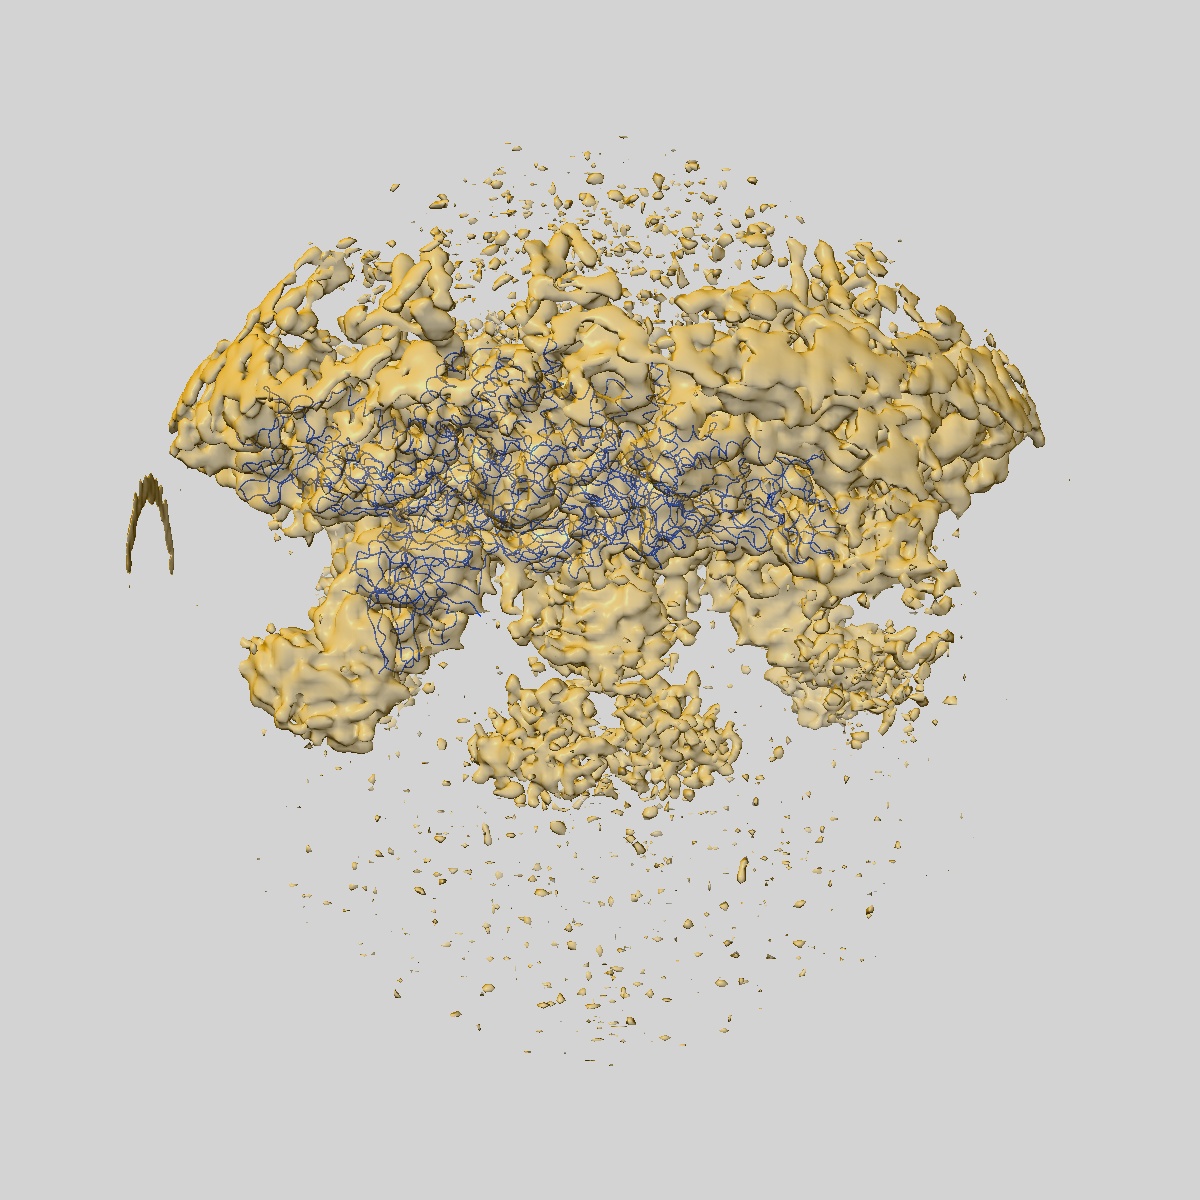

Cryo-EM structure of dengue virus serotype 3 strain 863DK in complex with human antibody DENV-115 Fab at 37 deg C (subparticle LLR-LRR)

Single-particle5.4 Å

Sample: Dengue virus serotype 3 strain 863DK in complex with human antibody DENV-115 Fab at 37 deg C

Fitted models: 8jn3

Ultrapotent human antibodies lock E protein dimers central region of diverse DENV3 morphological variants.